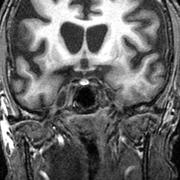

Behandling för Huntingtons bromsade sjukdomen markantForskare ser ut att för första gången ha hittat en behandling mot hjärnsjukdomen Huntingtons, rapporterar BBC och Stat News med hänvisning till en ny studie.24 september 2025, 14:06

Omni förklarar •Därför drabbas unga av demens – livsstilsfaktorerna som kan påverkaAllt fler yngre diagnosticeras med någon form av demenssjukdom. Inom 25 år pekar prognoserna mot att antalet med någon form av demenssjukdom kan ha fördubblats.Omni Mer